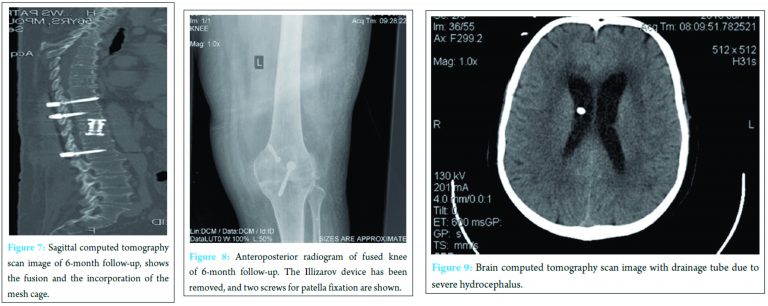

All sites required local debridement and secondary closure. The left knee fused completely 3 months following surgery. On the basis of antibiotic susceptibility pattern, quinolone and ceftriaxone were IV given. The patient received 3 months IV antibiotic treatment and was discharged with instructions for a monthly check of inflammatory markers. Antibiograms is the safe way for the antibiotics selection, although ciprofloxacin, 3rd generation cephalosporin, ampicillin, and chloramphenicol are the most common antibiotics in such infections. The IV administration was combined with our patient hospitalization due to his impaired general condition and the post-operative complications. The duration of the antibiotic treatment was determined on the basis of the evidence-based guidelines, to minimize relapse possibility. At the 6-month follow-up, CRP and ESR remained within normal limits. Radiograms and CT scan showed a good result of fusion in both sites (Fig. 7 and 8). The patient was free of pain, and he had started to return to his daily routine. There was not any sign of recurrence. Although 2 months later, our patient became anxious and his family found him with an altered state of consciousness and cognition. On admission to the hospital, our patient lost his consciousness and had to be intubated and transferred to intensive care unit. Brain CT scan revealed edema and hydrocephalus that required drainage tube installation (Fig. 9). The lumbar puncture of cerebrospinal fluid was indicative of viral infection. EEG showed slow waves and based on the previous medical history all possible cultures were taken. Blood cultures revealed again SE. Our patient did not recover from this meningoencephalitis, and his relatives decided to disconnect him from the ventilator on the day 11th being clinically dead. We believe that SE infection recurrence caused immunosuppression to this impaired patient making him unable to manage this central nervous system viral infection.